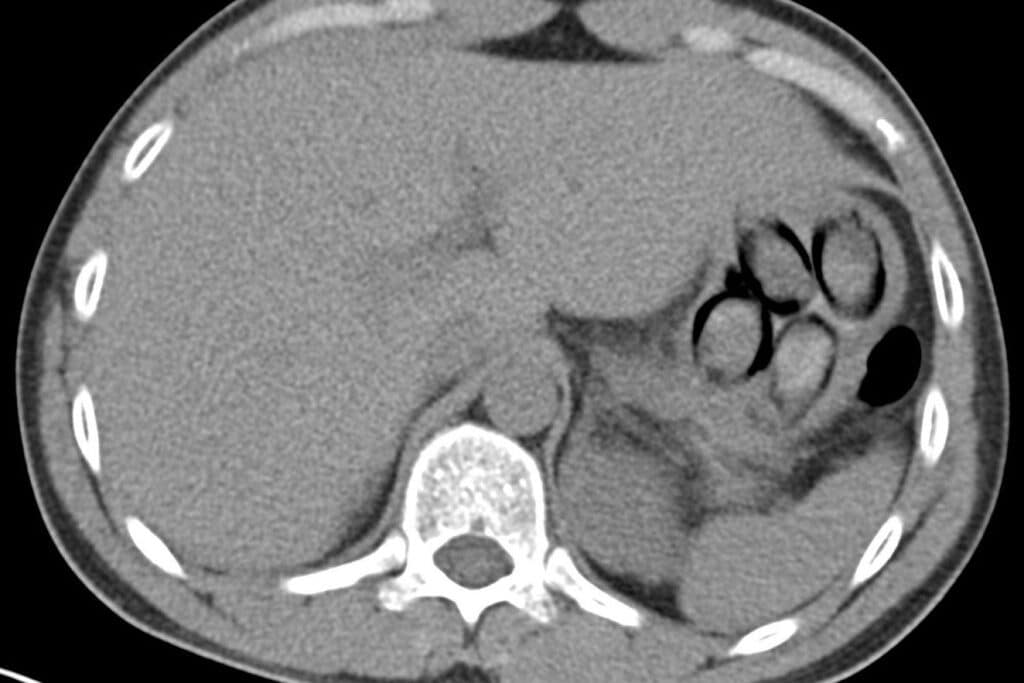

Eine Röntgenuntersuchung in einem Kölner Krankenhaus bestätigte den Verdacht: Im Magen des Niederländers waren mehrere Drogenpäckchen zu erkennen. Unter Überwachung schied der Mann anschließend sieben sogenannte Bodypacks mit insgesamt mehr als 100 Gramm Kokain aus.

| Bildhinweis: | Röntgenbild zeigt mehrere Kokainpäckchen im Magen des Niederländers (Archiv), Hauptzollamt Köln via |